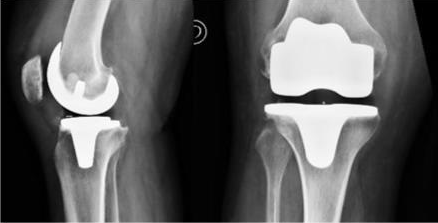

Existen actualmente tres tipos de prótesis de rodilla que permiten remplazar y repavimentar las superficies articulares de los compartimentos desgastados o destruidos:

- La prótesis total que concierne a los tres compartimentos de la rodilla: fémoro-tibial interno, externo y fémoro-patelar.

- La prótesis uni-compartiemental para el compartimento interno o externo.

Prótesis total de rodilla

La causa más frecuente de dolores de rodilla en los mayores es la artrosis de rodilla.

La prótesis total de rodilla está indicada cuando los tratamientos de fisioterapia y los tratamientos médicos y quirúrgicos conservadores resultan

ineficaces.

Esta intervención suprime los dolores relacionados con el desgaste, devuelve una movilidad satisfactoria a la rodilla y una calidad de vida confortable. Los resultados son generalmente muy satisfactorios en los pacientes de 70 años o más. En los pacientes más jóvenes y con una vida más activa (que solicitan durante más tiempo y más intensamente los implantes) se prefieren las intervenciones de cirugía conservadora como la osteotomía.

El objetivo de la intervención es suprimir los dolores y restaurar una buena alineación y un buen funcionamiento de la rodilla.